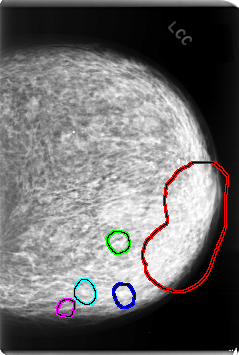

C_0078_1.LEFT_CC

LEFT_CC LINES 6032 PIXELS_PER_LINE 4056 BITS_PER_PIXEL 12 RESOLUTION 50 OVERLAY

FILE: C_0078_1.LEFT_CC.OVERLAY

TOTAL_ABNORMALITIES 5

ABNORMALITY 1

LESION_TYPE CALCIFICATION TYPE PLEOMORPHIC DISTRIBUTION CLUSTERED

ASSESSMENT 5

SUBTLETY 5

PATHOLOGY MALIGNANT

TOTAL_OUTLINES 1

BOUNDARY

ABNORMALITY 2

ABNORMALITY 3

ABNORMALITY 4

ABNORMALITY 5